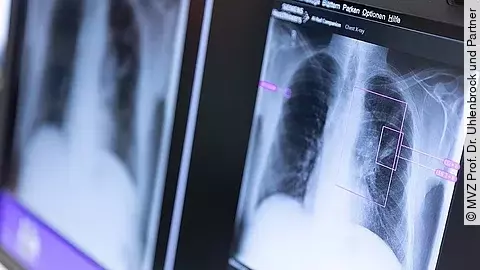

Lunit Insight CXR erkennt präzise zehn der häufigsten Befunde im Röntgen-Thorax, unterstützt das Tuberkulose-Screening und hat sich als klinisch effizient bei der Detektion von Pneumonien erwiesen, die ein erster Hinweis auf eine Covid-19-Erkrankung sein können. Die Lösung priorisiert Fälle mit Anomalien in einem Score und erleichtert die schnelle Triage normaler Fälle, sodass Radiologinnen und Radiologen sich auf auffällige Befunde konzentrieren können.